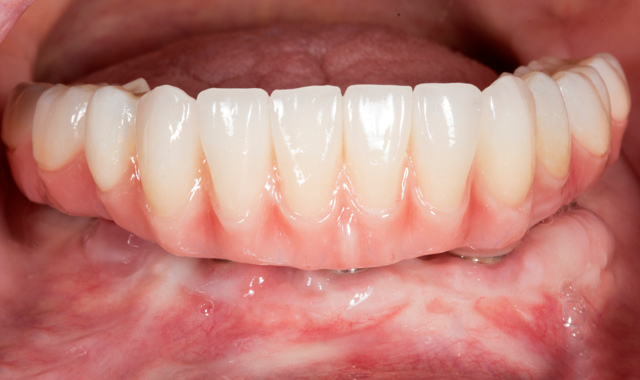

However, the fabrication is technique sensitive and should follow the appropriate clinical and laboratory steps discussed in this case study. The patient outcome showed high success in function, esthetics, phonetics and high patient satisfaction (Figs. 16-17).

Fig. 16

Figure 17